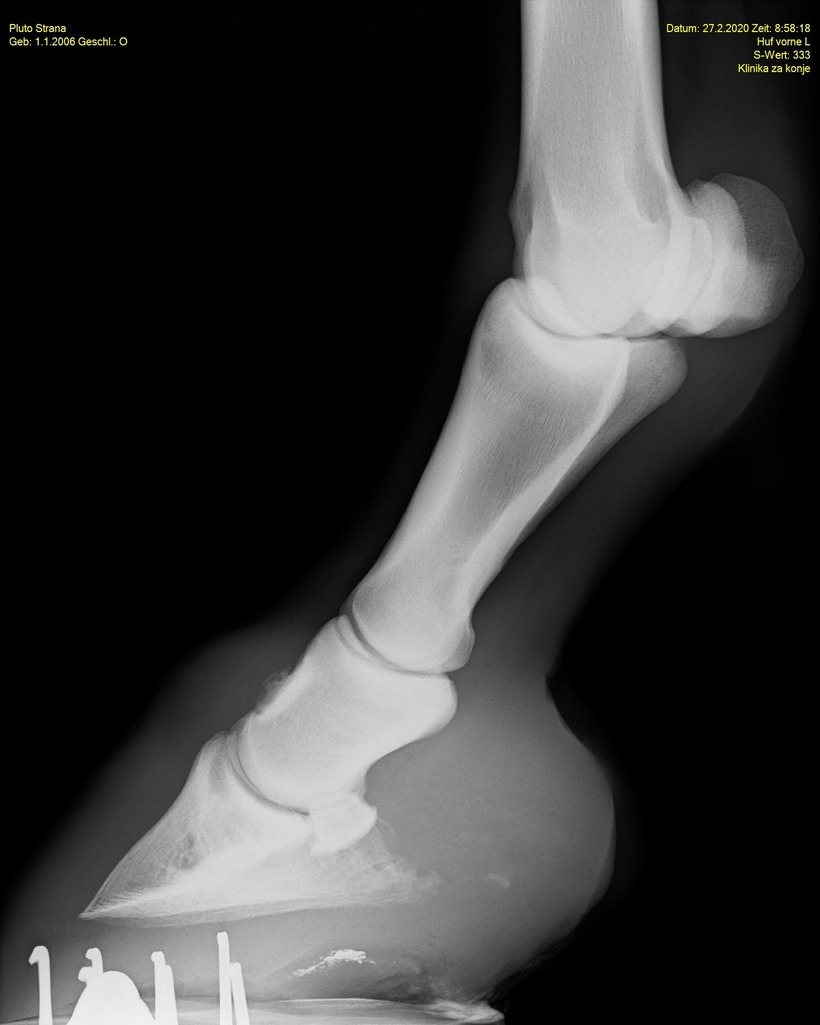

Prva tehnika diagnosticiranja je rentgensko slikanje. V veterini se pogosto uporablja, saj gre za neinvazivno, hitro, preprosto za uporabo in poceni tehniko, vendar ima žal tudi svoje pomanjkljivosti. Z rentgenskim slikanjem namreč primarno ugotavljamo spremembe kostnega tkiva, ki večinoma v zgodnji fazi procesa še niso opazne. Rentgensko slikanje tako pride v poštev šele takrat, ko je proces že napredoval in so spremembe vidne.